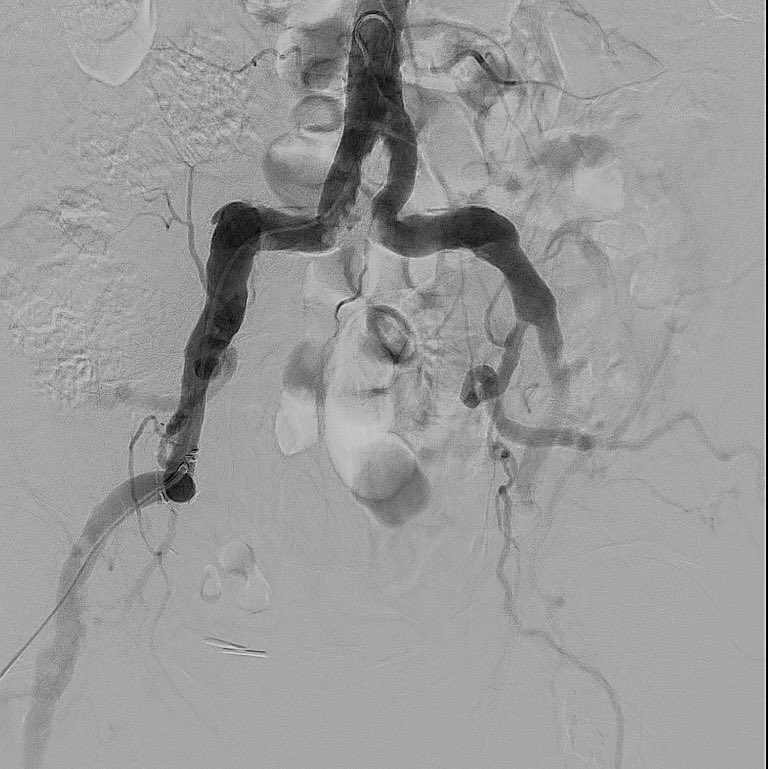

66 ym Ongoing sever chest pain HR 120 BP 90/60, EF 33 % Will MCS with Impella make a difference in outcome of PCI in this patient. If Impella is not available (>95% of cath labs in India) would you still recommend PCI or will you refer him for emergency CABG #DanGerShock